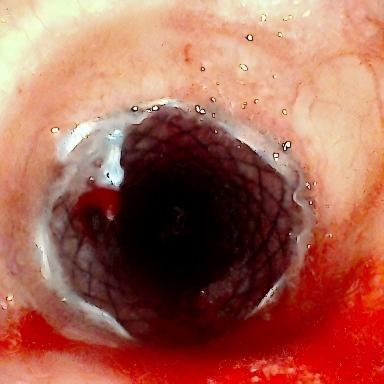

患者为75岁女性,因“反复咳嗽咳痰、气促10余年,加重3月”,于3月3日入住湘雅三医院呼吸与危重症医学科。入院时患者呼吸困难症状严重,CT检查提示气道存在严重狭窄,随时面临窒息风险。经管床医生杨红辉副主任医师评估,患者气管狭窄情况复杂:最狭窄处管腔直径仅剩1-3mm,科室最细的4.0mm支气管镜也无法通过;狭窄位置极低,下缘距隆突仅1.6cm,意味着无法通过气管切开绕过病灶;狭窄处周围组织的CT值高达60-70Hu且无强化,因而直接植入支架存在无法撑开或加重堵塞的风险;同时,患者无法耐受全身麻醉,仅能采用利多卡因进行表面麻醉,操作难度较大。

为制定救治方案,杨红辉副主任医师立即启动全院大会诊,邀请ICU、麻醉科、放射科等科室专家共同讨论。会诊过程中,治疗团队面临两难抉择:一种方案是直接植入支架,但狭窄部位组织坚硬,支架可能无法撑开反而将气道彻底堵死,导致患者当场窒息;另一种方案是先行球囊扩张再植入支架,但操作时间过长,患者在严重缺氧状态下难以耐受。经综合研判,呼吸科杨红辉副主任医师、ICU何智辉主任、麻醉科廖琴主任提出在ECMO支持下实施气管支架植入术的方案,通过ECMO提供体外生命支持,保障介入操作过程中的氧合需求。

方案确定后,ICU团队为何智辉、邢伟、邓龙天为患者建立体外生命通道;呼吸介入团队孟婕、杨红辉、刘建明、邹丽君、贺一峻等通过球囊对狭窄部位进行预扩张,随后在距隆突仅1.6cm的低位气道精准植入支架。支架贴合良好,气道顺利开通,全程操作约1.5小时。患者当晚撤离ECMO,次日从ICU转回普通病房。后续肺泡灌洗液检测显示,患者大气道狭窄的原因为气管结核导致的瘢痕性狭窄。